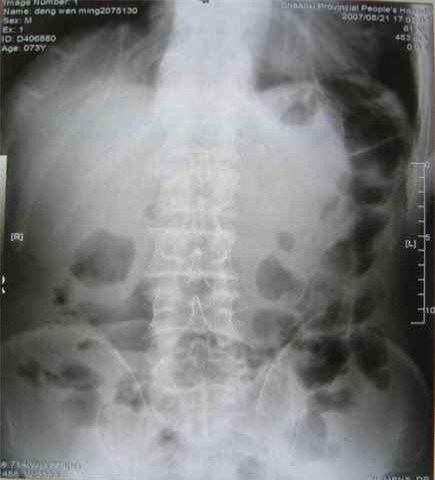

Hội chứng tắc ruột có thể dẫn đến tử vong (Ảnh: Internet)

Nếu không xử lý kịp thời, bệnh tình sẽ có biến chứng (Ảnh: Internet)